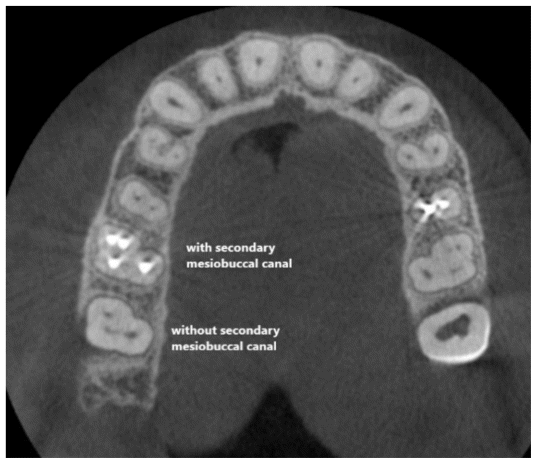

A total of 41 CBCT scans (132 maxillary first and second molars) were evaluated. All CBCT scans were obtained with the ProMax 3D CBCT scanner (Planmeca, Helsinki, Finland) using a voxel size of 0.15 × 0.15 mm, a tube potential of 84 kV, and a tube current of 9 mA. The images were saved, and the MAR algorithm with medium intensity was applied to them in Romexis version 3.8.0 software; this series of images was also saved. The images were then randomly coded, and two endodontists were asked to evaluate them for the presence/absence of MB2 in the maxillary first and second molars, based on the position of the first mesiobuccal canal (MB1). In the presence of MB1 at the center of the mesiobuccal root, the possibility of MB2 would be excluded, and the tooth would be excluded from the study (Campo (4) Figure 1).

The two endodontists also evaluated the visibility of MB2 in maxillary first and second molars on each CBCT image in the apical, middle, and coronal thirds according to the presence/absence of restoration or presence of an artifact-generating factor in the respective tooth or adjacent teeth, and also presence/absence of root filling in the respective tooth or adjacent teeth (Figure 2). The observers used all CBCT sections (axial, sagittal, and coronal) for their assessments. In the event of a disagreement between the two observers, a radiologist would be consulted. The observers reported the visibility of MB2 using a 5-point Likert scale as follows, (10):